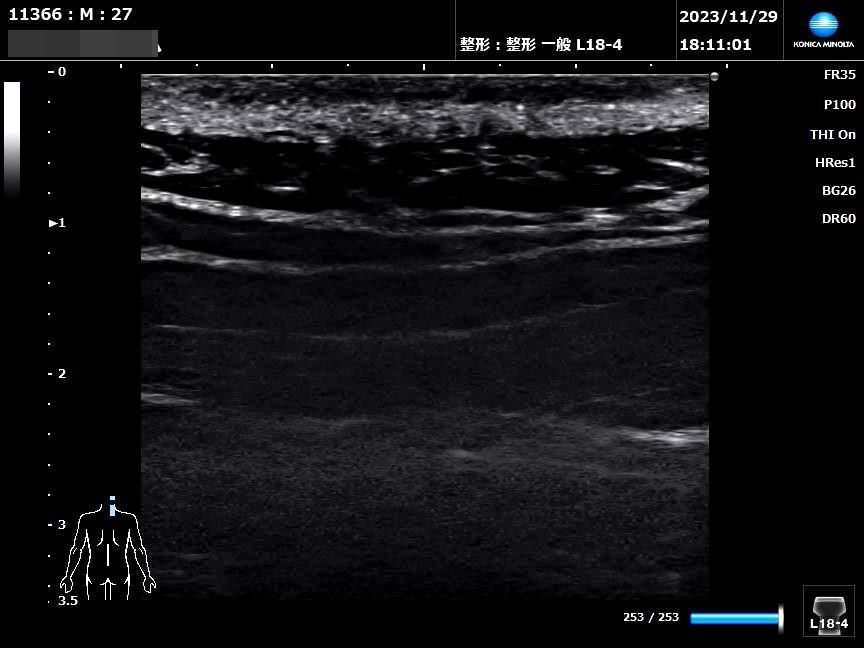

超音波エラストグラフィー(Elastography)は、エコー(超音波)技術を用いて肝臓や乳腺などの組織の「硬さ」を非侵襲的(体に負担をかけず)に画像化・数値化する最新の検査法です。

従来の超音波検査(Bモード)では描出できなかった「組織の硬さ(弾性)」を可視化・定量化する画像技術です。

*超音波エコー観察サンプル画像